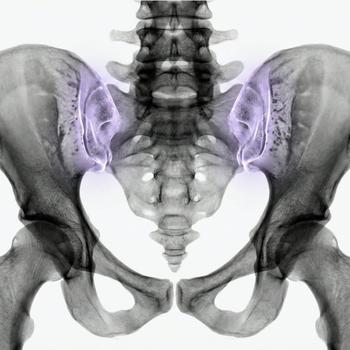

Arthritis occurs when joint cartilage breaks down faster than the body can repair it, resulting in an imbalance in the joint. This imbalance can cause a condition called joint failure where joint function deteriorates and pain and stiffness can occur. Osteoarthritis is a chronic disease that usually develops over time and can affect various joints in the body, including the knees, hips, hands and back.

The symptoms of osteoarthritis usually develop gradually over time. They can be intermittent, with periods of more pronounced discomfort and periods of milder symptoms. It is important to note that osteoarthritis can affect various joints in the body, including the fingers, toes, knees, hips, back, shoulders and jaw. In case of inflammation of the articular cartilage, the joints may become red and warm. In addition, small nodules or bony growths, known as Heberden's nodules, may form on the outermost joints of the fingers, which may cause pain but are not dangerous in themselves. To manage osteoarthritis and relieve its symptoms, it is important to seek medical advice and explore appropriate treatment.